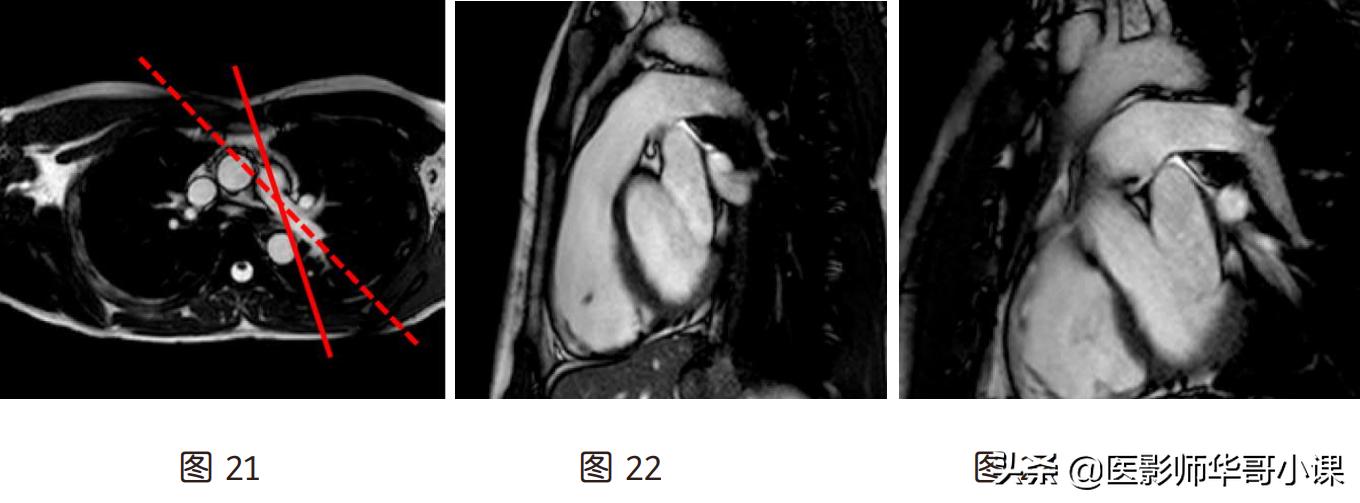

(11)右室流入流出道(图 32):通过心尖、三尖瓣口中点及肺动脉三点定面